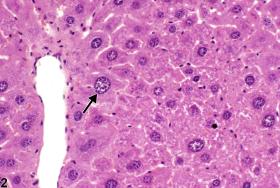

Liver, Hepatocyte - Karyomegaly

Karyomegaly in a female B6C3F1 mouse from a subchronic study.